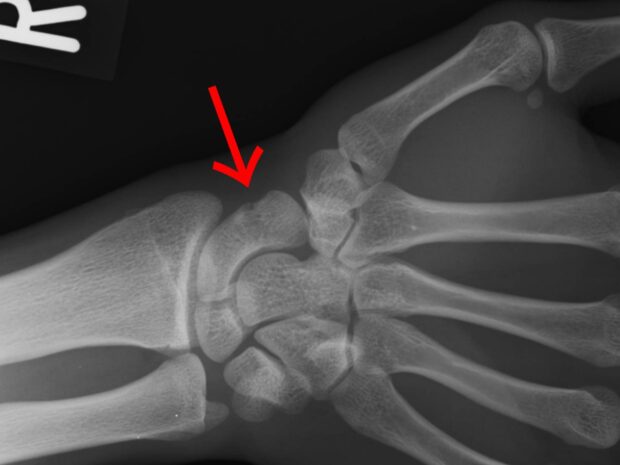

舟状骨骨折は、転倒して手をついた際に起こりやすい骨折の一つです。

しかし、初期のレントゲンでは写らないこともあり、

捻挫として見過ごされることが少なくありません![]()

手の専門医にて精査を行ったところ、やはり舟状骨(遠位1/3)骨折との診断でした…![]()